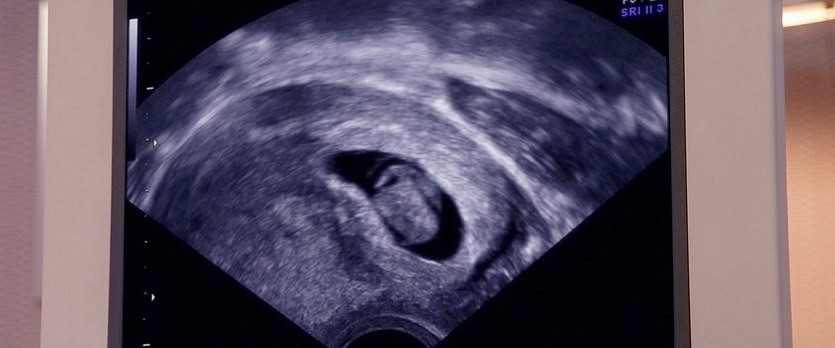

圖片名稱:Hello.Babies.2014_05738

圖源尺寸:Blu-ray 1080p